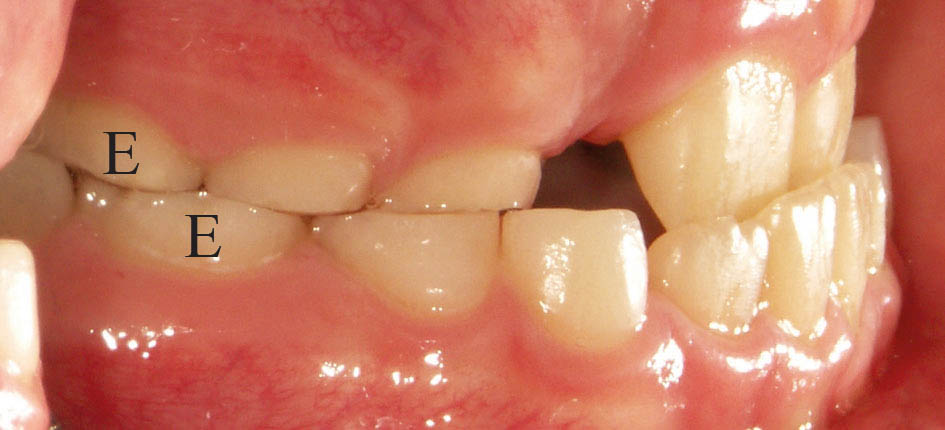

برای ارزیابی روابط افقی دیستال دندانهای E بالا و پائین را نگاه کنید.

اگر دیستال E پائین جلوتر از دیستال E بالا باشد (شکل 19-5) بیمار کلاسIII میشود. بعضی مواقع کلاسI هم میشوند.

اگر دیستال E پائین عقبتر از بالا باشد (شکل 20-5) بیمار حتماً کلاسII میشود.

شکل 19-5: دیستال E پائین جلوتر از دیستال E بالاست، لذا بیمار در آینده کلاسIII میشود

شکل 20-5: دیستال E پائین عقبتر از دیستال E بالاست، لذا بیمار در آینده به احتمال زیاد کلاسII میشود